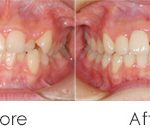

前歯のガタガタを気にして来院されました。人前でお話をするお仕事のため、なるべく目立たない矯正治療をご希望されました。

右側の噛み合わせに違和感を感じており、見た目だけでなく噛み合わせも改善したいと考えています。

歯並びのアーチを全体的に大きくし、部分的に歯の大きさを少しずつ小さくすることで歯を並べるスペースを作りました。インビザラインの透明なアライナーは、治療期間中、周りに気を使うことなく順調に治療が終わりました。

噛み合わせは左右対称的に噛めるようになり、治療前の違和感がなくなりました。